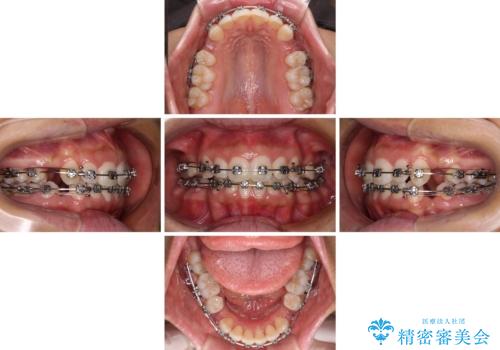

- 矯正装置

- メタルブラケット

- 出っ歯で唇が閉じにくいとのことで来院された患者様です。

顎先に力を入れないと唇が閉じきれない口元であったので、上下左右の第一小臼歯4本を抜歯して、ワイヤー装置にて矯正治療を行うこととしました。

費用を抑えるため、金属の装置を選択されました。